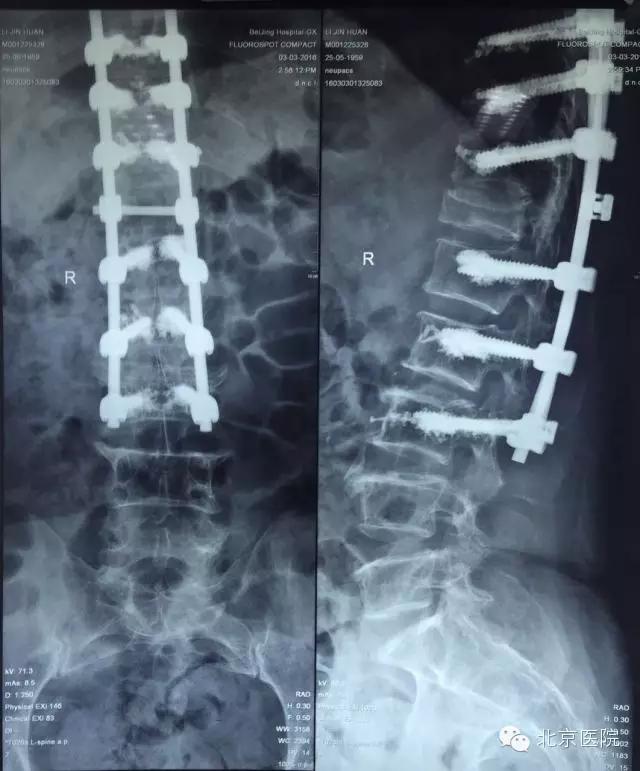

在完善了术前检查后,经过骨科全科专家会诊、脊柱组组内讨论后,制定了适合该患者的详细手术方案。通过术前测量,该患者的后凸畸形成角角度约60°,由于骨折后楔形变的胸12椎体前缘高度下降太多,导致脊柱后凸的顶点位于胸12椎体,故采取了经胸12椎弓根椎体截骨矫形手术。这种手术通过将变形的椎体截去三角形的一部分,把椎体后缘的高度降低到跟前缘一样,从而把后凸变形的脊柱“掰直”,然后通过椎弓根钉棒系统牢牢地将脊柱固定在符合生理力线的位置上,有效的缓解了胸背部的肌肉张力,从而大大缓解了患者的腰背部疼痛。该手术由孙常太副主任、申剑副主任医师、王强副主任医师等组成的治疗组实施,在手术麻醉科的喻震、郭晓曦等同仁的全力配合下,术中精心操作,小心避开了极易损伤的脊髓圆锥部分,顺利的完成了截骨、矫形、固定等步骤。术后该患者在骨科高凡护士长带领的优秀护理团队的精心照料下,安全康复,术后第6天即下地活动,下肢神经功能完全正常,腰背部疼痛得到了明显地缓解,并于术后第9天顺利出院回家。

经椎弓根脊柱截骨矫形手术是一种适用于脊柱后凸、侧弯畸形患者的矫形手术,国内外最常见于青少年脊柱侧弯或年轻人结核性、强直性脊柱炎后凸的矫形治疗,目前罕见有报道用于老年骨质疏松患者的矫形手术治疗。该手术操作复杂、难度大,容易损伤脊髓神经,术后患者也有一定的康复护理难度。我院骨科在老年脊柱患者手术例数上在全国遥遥领先,积累了大量的骨质疏松患者手术经验,在该患者的治疗中得到了有效地应用——为加强内固定强度,采用了骨水泥灌注+椎弓根螺钉内固定技术,可更加有效地避免术后内固定物松动。近几年我院骨科已经成功完成了十几例老年后凸、侧弯畸形患者的经椎弓根脊柱截骨矫形术,积累了丰富的经验,尤其是在高龄患者的脊柱畸形矫形方面取得了一定的成绩,以后必定能够通过技术的进步,经验的积累更多的为老年脊柱后凸、侧弯畸形的患者带来福音!